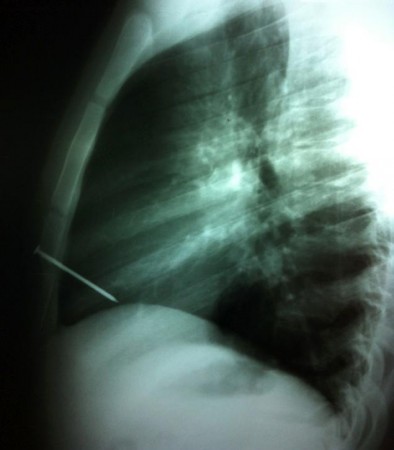

Аргентинадағы ағашшы жігіттің жүрегіне 7 см шеге қадалып, Аргентина астанасы Буэнос-Айрестегі бір емханаға жеткізілген. Тексеру нәтижесі оның өмірінен үмітін үзген адамдарды таң қалдырып, бұл жігіт аман қалған. Таң қаларлық себеп те бар, басында Х нұры арқылы түсірілген суретті көргенде дәрігерлер біржола үмітін үзген. Тек тынысының әлі тоқтамағаны үшін шұғыл түрде жасалған екі сағаттық ота барысында бұл азаматтың жүрек соғуы қалпына келген екен. Мұндай ұзындықтағы үшкір қару көкірек бөліміне кіріп, жүйеден жүректі зақымдап, сондай жағдайда да аман қалған қазірге дейін әлемде үш-ақ адам бар екен. Бұны дәрігерлер «Аргентинаның емдеу саласындағы тұңғыш оқиға» дейді.

Сурет: baidu.com